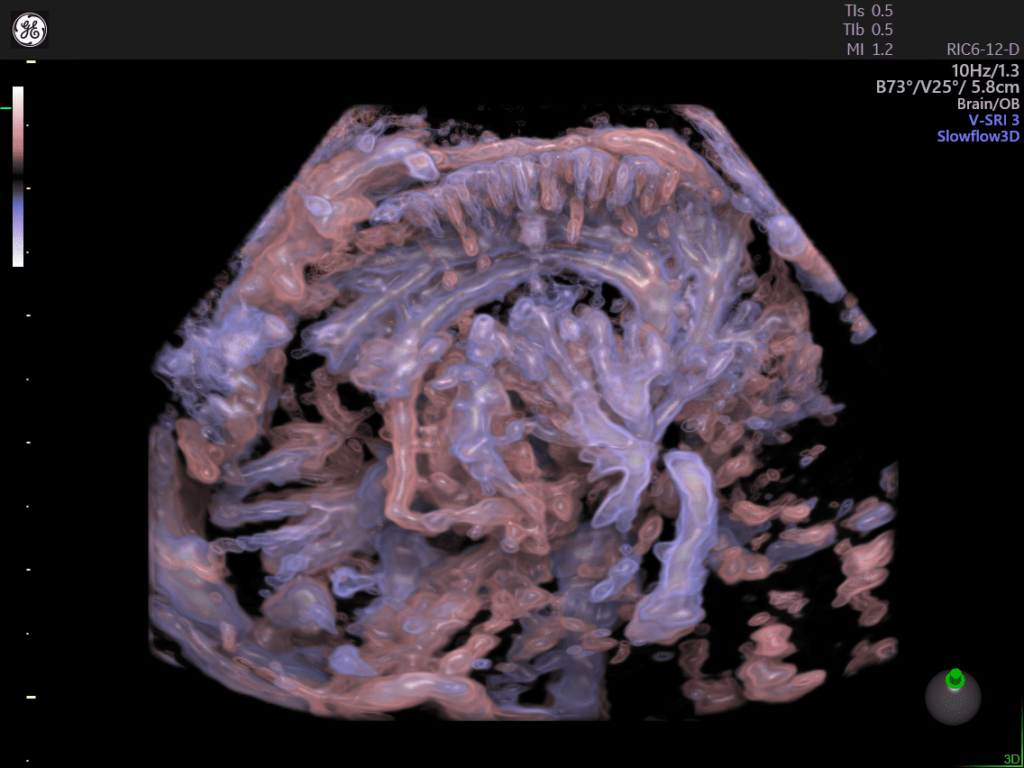

Slowflow 3D: È possibile abbinare le varie tecnologie Volume Ultrasound integrate nella piattaforma per uno studio approfondito delle strutture vascolari del cervello fetale, dei vasi addominali e in applicazioni ginecologiche, quali lo studio dell’adenomiosi tramite Slowflow 3D.